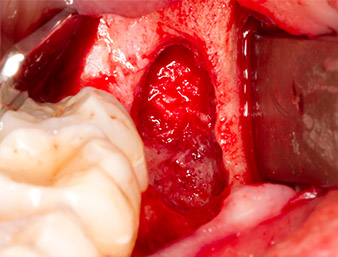

It was then possible to remove the approximately six-millimetre-long root remnant in one piece with the P1 attachment (Fig. 11).

Periapical inflamed tissue was also removed very carefully with a manual excavator. Fig. 12 shows the empty alveole with exposed inferior alveolar nerve.